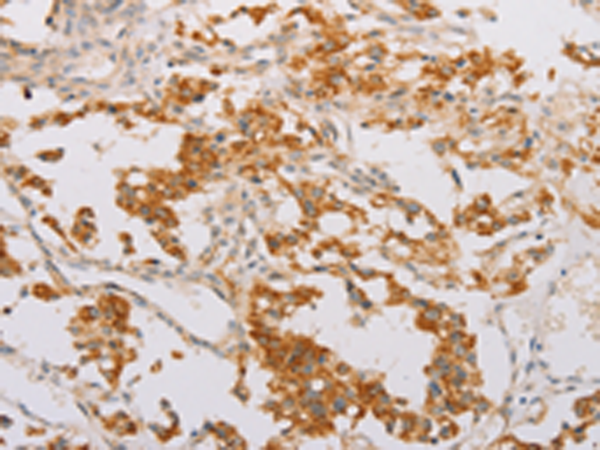

分类: 科研抗体货号: P08010别名: ZFYVE11; FYVE-DSP2应用: IHC反应种属: Human, Mouse